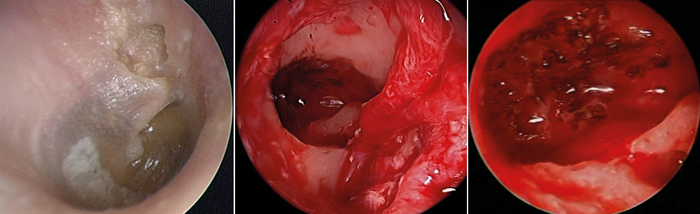

Congenital cholesteatoma confined to the mesotympanum provides a perfect opportunity for TEES, not least because no challenging reconstruction of the tympanic membrane is required (Figure 2). Acquired cholesteatoma arises from the pars tensa more commonly in children than the pars flaccida, so commonly extends into retro-tympanic recesses.

Figure 2. Congenital cholesteatoma in the antero-superior quadrant of the left middle ear in a 3.9-year-old child (left).

This was removed using totally endoscopic surgery through the ear canal (right).